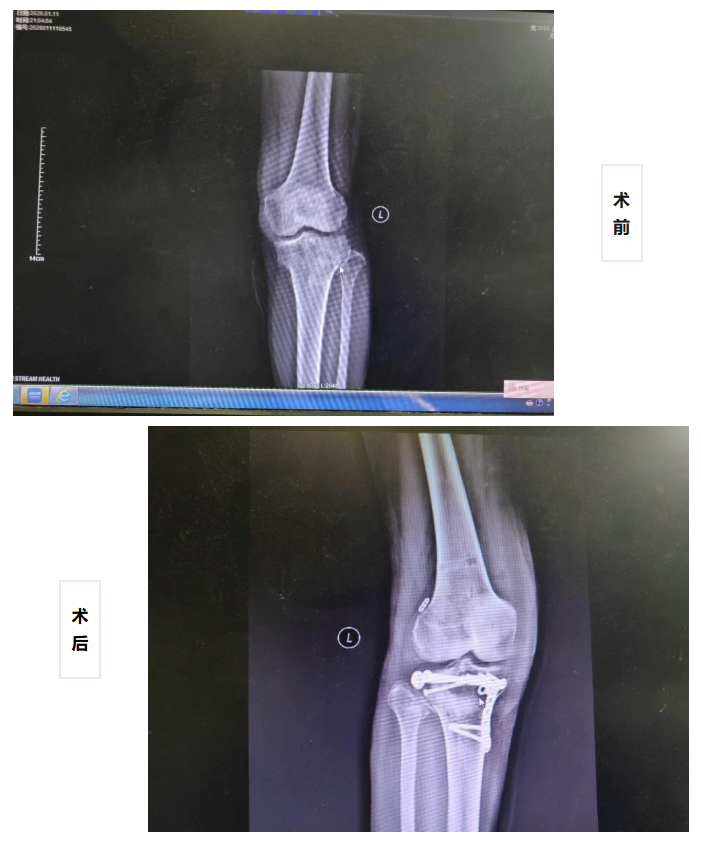

近日,我院骨外科团队为复杂膝关节损伤患者实施V型胫骨平台骨折复位内固定联合前交叉韧带重建术。该手术一次解决了患者左侧胫骨平台、腓骨小头骨粉碎性骨折与前交叉韧带断裂两大问题,打破了传统手术需要分两次进行治疗的模式。

手术中,骨外科手术团队凭借精湛的关节内复位技术,将V型骨折块精确复位、内固定,重建平整的关节面;随后在已经稳定的骨隧道基础上,完成前交叉韧带的取腱、编织与植入固定。术后患者恢复良好,已开始功能康复锻炼。